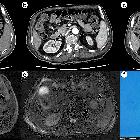

CT

- tend to occur in the head and body of the pancreas

- well-demarcated

- hypoenhancing mass with a hypervascular capsule

- may demonstrate hemorrhage or cystic degeneration

- fat attenuation may be present

MRI

Signal characteristics include

- T1: hypointense

- T2: hyperintense

- T1 C+: heterogeneous enhancement

- T1 FS: macroscopic fat intensity may be present (saturates on a fat sat sequence)